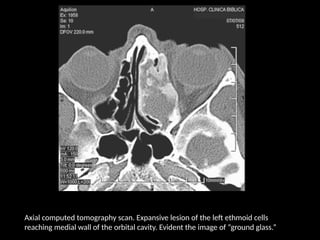

Axial computed tomography scan. Expansive lesion of the left ethmoid cells

reaching medial wall of the orbital cavity. Evident the image of “ground glass.”